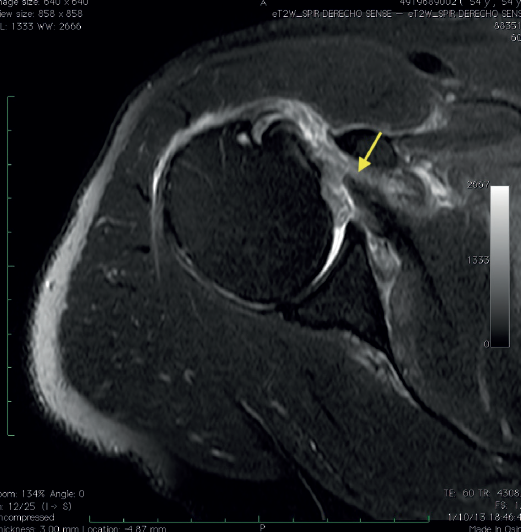

Radiological assessment included preoperative magnetic resonance imaging (MRI) of the affected shoulder, reviewed independently by the operating surgeon. MRI was used to confirm the diagnosis (Figure 1), classify the tear according to Lafosse classification, assess tendon retraction, fatty infiltration (Goutallier classification) on the sagittal plane, rule out advanced degenerative changes, and evaluate associated biceps pathology (Figure 1).

Figure 1. Axial magnetic resonance image of full-thickness acute subscapularis tear. Arrow: Torn subscapularis tendon.